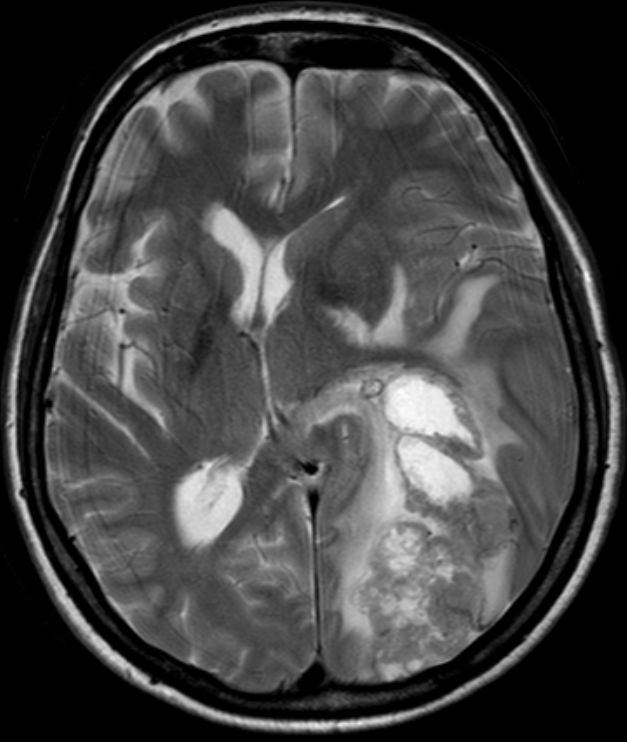

| Hirnmetastase | 48-jährige Frau, die vor 4 Jahren ein DLBCL Stadium IVa mit Bulk rechts inguinal, Lymphknoten mediastinal axillär links, Milzvergrößerung und pulmonale Infiltration hatte. 8mal R-CHOP, RT der rechts inguinalen Lymphknoten mit 26 Gy. Vor 5 Monaten Tumor linker Hilus und Hirnmetastase links occipito-parietal: Histologie: großzelliger neuroendokriner Tumor. Entfernung der Hirnmetastase, RT Neurocranium. 6 x Carboplatin/Etoposid: PR des Lungentumors, vitaler Resttumor des Gehirns | |||||||||||||||||||

MRT T1 FFE: Ausgedehnte Matastase li occipital.![]() | |||||||||||||||||||

MRT MIP T1 FFE![]() | |||||||||||||||||||

MRT MIP T1 FFE![]() |